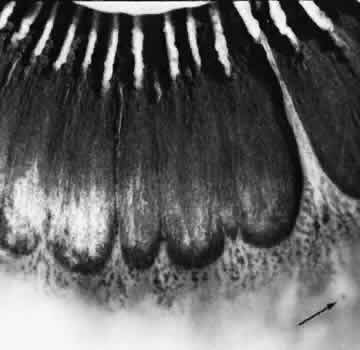

ZONULAR-TRACTION RETINAL TUFT

The zonular-traction retinal tuft always projects from the retinal surface internally and anteriorly toward the zonule (Fig. 40). Usually single and located within the vitreous base, zonular-traction retinal tufts are joined to zonular fibers at the apex; the tufts, which vary in length and thickness, are associated with a broad range of trophic and tractional alterations at the retinal end of the process. Histopathologic changes include zonular attachments at the apex, neuroglial cells within the tuft, and degeneration with retinal thinning at the base (Fig. 41). Retinal holes and tears result from the combination of trophic changes at the base and traction resulting from zonular fibers. Within the vitreous base and posterior to it, zonular-traction tufts may be associated with partial-thickness or full-thickness retinal tears that can occur in the absence of posterior vitreous detachment.

Fig. 40. Zonular-traction tuft of the peripheral retina. Tuft is drawn at an acute angle from the retinal surface toward the ciliary body and shows microcystic degeneration anteriorly. Posteriorly, the tuft splays; the retina at its base shows marked trophic change, including three full-thickness holes (arrow). (× 20.)

Fig. 41. Zonular-traction tuft (arrow) drawn at an acute angle from the retinal surface toward ciliary body with dense-staining glial cells along surface. Base of tuft is microcystic and has full-thickness trophic hole. (Hematoxylin-eosin; × 150.)

Zonular-traction tufts are present at birth and detected with equal frequency in patients of all ages; they are noted in 15% of patients, are bilateral in 15% of affected people, and thus are evident in 9% of all eyes (see Table 3). These tufts are most common in the nasal quadrants, usually attached to the retina less than 0.5 mm posterior to the ora serrata and only infrequently attached to the retina posterior to the vitreous base.27,36

Clinical examination of the peripheral fundus reveals zonular-traction tufts in patients of all ages. These lesions are distinguished from noncystic and cystic retinal tufts by their greater size, sharp anterior angulation, and close proximity to the ora serrata. Zonular-traction tufts are a significant cause of small, round retinal holes in the extreme periphery of the retina. Although retinal holes within the vitreous base are considerably less likely to produce retinal detachment than holes posterior to the vitreous base, surgical aphakia or pseudophakia, which necessarily involves some form of zonular traction, is associated with an increase in the frequency of retinal detachment, which is likely to be related to small retinal breaks in the nasal periphery.36,37